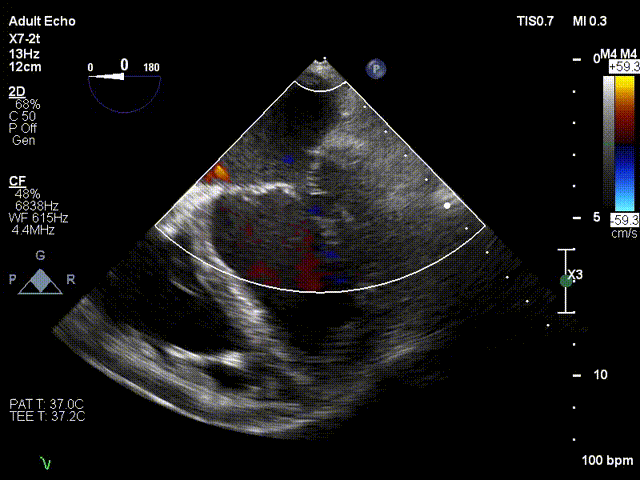

术前超声评估:

术前TTE超声提示二尖瓣大量反流